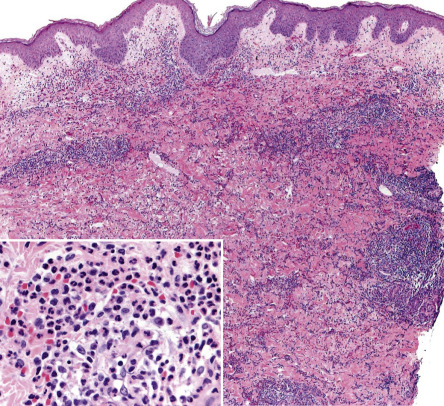

The neutrophilic dermatoses constitute a heterogeneous but linked spectrum of diseases , with significant overlapping histopathologic findings and similar pathogenic mechanisms and therapeutic approaches. They are often associated with underlying internal diseases, which may have significant morbidity and mortality. Histologically, these disorders are characterized by perivascular and diffuse neutrophilic infiltrates without any identifiable infectious agents ( Fig. 26.1 ). The cutaneous manifestations vary, from urticarial plaques and vesiculopustules to nodules and ulcers. It is noteworthy that there may be several different types of lesions in the same patient. The dermatosis may be localized or more widespread, and, in an occasional patient, similar sterile neutrophilic infiltrates may occur in other organs including the eyes, joints, bones, lung and kidney. The neutrophilic infiltrate may be most prominent in the epidermis, dermis, or even the panniculus. Distinct entities have been defined by the nature of their clinical and histologic presentations as well as their associated diseases.

The histopathologic features are contingent upon the type of cutaneous lesion sampled. The characteristic histologic presentation is a diffuse nodular and perivascular neutrophilic infiltrate without evidence of vasculitis ( Fig. 26.5 ), although occasionally leukocytoclastic vasculitis (LCV) can be observed. Leukocytoclasia with endothelial swelling, but without the fibrinoid necrosis that fulfills the criteria for LCV, is the usual finding. Occasionally, the dermal infiltrate may extend into the subcutis, creating a septal or, less frequently, a lobular panniculitis. Isolated neutrophilic panniculitis has been described.

In general, epidermal changes are not significant. However, neutrophils occasionally invade the epidermis, producing subcorneal pustules, and they may also infiltrate the adnexa. In the setting of significant edema, there can be epidermal spongiosis and sometimes reticular degeneration as well as intraepidermal and subepidermal vesiculation.

Three histologic variants of Sweet syndrome, histiocytoid, lymphocytic and eosinophilic, have been increasingly recognized. The histiocytoid variant is characterized by a dermal, and sometimes subcutaneous, infiltrate composed of histiocyte-like immature myeloid cells . These cells have myeloperoxidase activity ( Fig. 26.6 ) and must be distinguished from those of leukemia cutis. The lymphocytic variant is often associated with, and sometimes precedes, underlying myelodysplasia . More recently, an eosinophilic variant has been described .